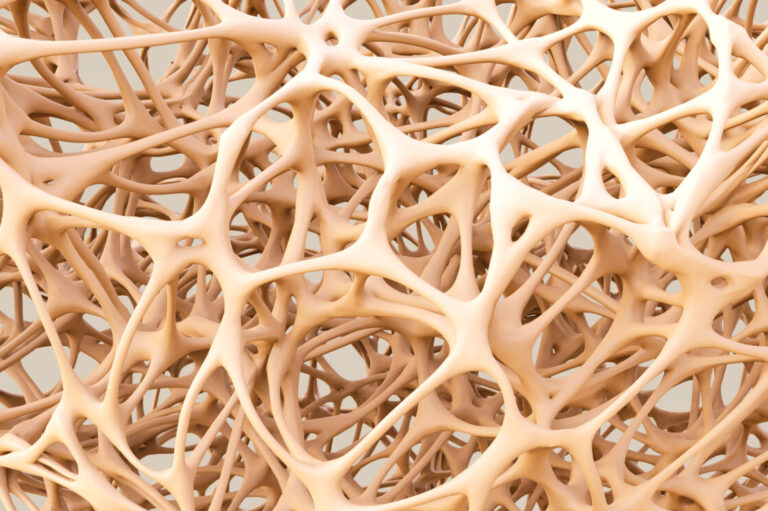

Aspetti istopatologici dell’osteomalacia

Sebbene l’osteomalacia possa essere il risultato di diversi meccanismi patogenetici, è caratterizzata da caratteristiche istologiche comuni. I segni istologici dell’osteomalacia compaiono se la causa che porta a un’alterata mineralizzazione persiste nel tempo. La sequenza di eventi formazione ossea-mineralizzazione-riassorbimento è il processo coordinato che si verifica in ogni unità di rimodellamento del tessuto scheletrico maturo, sia nei giovani che negli adulti, che richiede e fornisce i minerali dal e al compartimento extracellulare, rispettivamente. Classicamente riferita alle forme vitamina D-dipendenti, una classificazione di osteomalacia è stata attribuita all’evoluzione delle alterazioni ossee rilevate istologicamente. Nelle prime fasi del disordine del metabolismo minerale, gli attori chiave del processo di mineralizzazione, cioè ormoni ed enzimi, si adattano al fine di fornire allo scheletro una quantità sufficiente di minerali per formare e sostituire la matrice mineralizzata precedentemente riassorbita e per correggere eventuali anormalità.

Nello stadio precoce della malattia non si rilevano aberrazioni istopatologiche nello scheletro, ma possono essere presenti sintomi generali dovuti a un’anomalia metabolica sistemica (stadio I, o pre-osteomalacia). Se l’alterazione metabolica persiste e non può essere annullata da adattamenti metabolici, non si formano cristalli di idrossiapatite e la matrice non può essere mineralizzata.

L’accumulo progressivo di osteoide, insieme a una mineralizzazione residua, è tipico dello stadio II. Lo stadio III è la completa cessazione della mineralizzazione con una notevole quantità di osteoide, che corrisponde al tradizionale quadro istologico dell’osteomalacia conclamata. Dal punto di vista istomorfometrico, la formazione dell’osso è totalmente inibita, come dimostrato dall’assenza di captazione di tetraciclina, con diminuzione del volume osseo per volume di tessuto (BV/TV), aumento dello spessore, volume e superficie dell’osteoide (larghezza dei filamenti osteoidi >15 m). La quantità di osteoide è normalmente proporzionale al grado e alla durata del disordine del metabolismo minerale.

Ad oggi, la diagnosi di osteomalacia è principalmente clinica; la valutazione sistematica della qualità dell’osso nell’osteomalacia, al fine di trovare modelli specifici di questa malattia, aiuterebbe a perfezionare la diagnosi radiologica. Infatti il punteggio osseo trabecolare (TBS), un indice per dedurre la microarchitettura ossea nelle immagini DXA, potrebbe aiutare a differenziare l’osteomalacia dall’osteoporosi in tempi più rapidi.